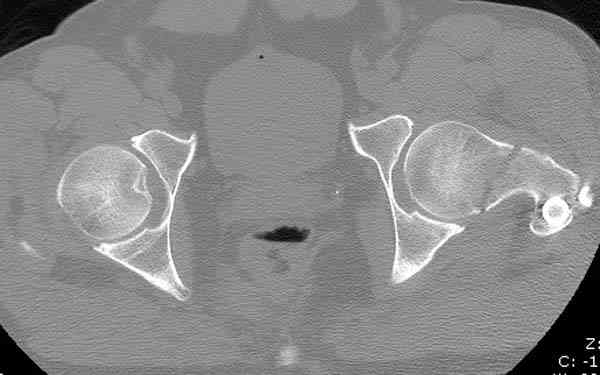

Кроме обязательных ренгенологических снимков тазобедренного сустава, при подозрении на перелом шейки рекомендуем Компьютерную Томографию.

Здесь представлены снимки больного 65 лет, поступившего с диагнозом перелом

бедра после автоаварии.

В первый же день произведено антеградное штифтованием DePuy Trochanteric Nail.

На второй день (7) обнаружен пропущенный перелом,

сделаны Компьютерная Томограмма

и проведены шурурпы через и спереди штифта без удаления.

Послеоперационные снимки